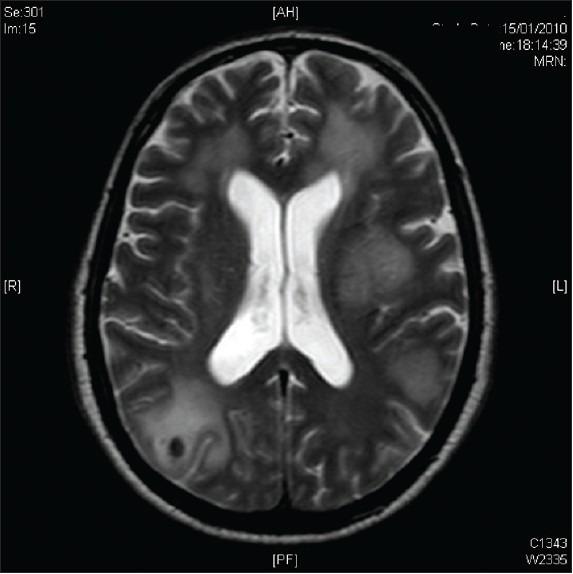

一例发生于脑部的大B细胞血管内淋巴瘤。

A case of large B-cell intravascular lymphoma in the brain.

Intravascular lymphoma is a rare and fatal disease that can have central nervous system (CNS) manifestations. It is usually a diagnosis made postmortem. This is partly due to its varied presentation, which lends itself to the complexity of diagnosis.

We report a rare case of intravascular lymphoma in the brain found antemortem.